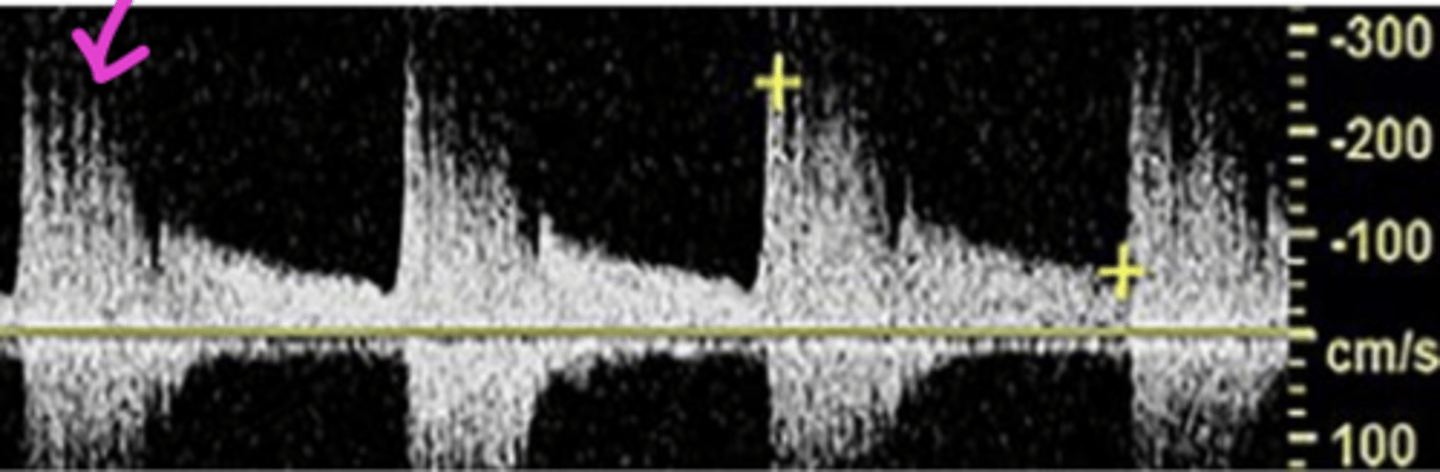

Dampening/Tardus Parvus

-upstroke/downstroke equal

-overall low velocities

-never normal (indicated stenosis proximal to insonation site)

Turbulence

-forward and reversed (bidirectional) flow

-marked spectral broadening

-variable velocities

-post stenosis